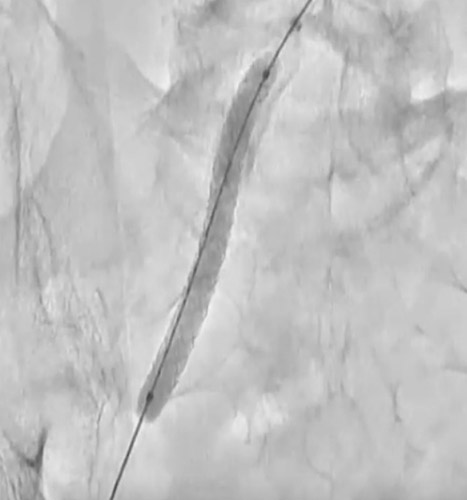

EIAの動脈瘤部にはカバードステントを留置することにした。6gワイヤー(0.014“)のままカバードステントのデリバリーを試みるが、バックアップが弱くEIAまで到達できなかった。6gワイヤーからサポート性の高い0.018ワイヤーに交換したが、ワイヤーが末梢まで到達できなかった。ラジフォーカスガイドワイヤーMスティッフ(0.035”)に交換することでサポート性を更に高めてデリバリーをし、カバードステントがIIA入口を塞がないように出来るだけ奥までデリバリーして留置した(図5)(図6)。

その際、R2P SlenGuideと止血弁の組合せでは、R2P SlenGuide先端からカバードステント本体部分を突出させるにはほとんど余裕がなかった。ガイドカテ全長とステントグラフト長の組み合わせには注意が必要と考えられた。